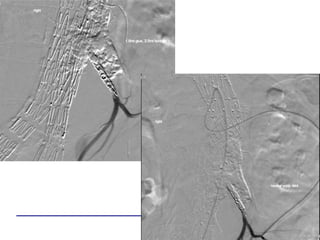

ONYXGLUE

Embolisation transartérielle

Guide de pression 0.014’’

20 G needle0.014’’ PressureWire